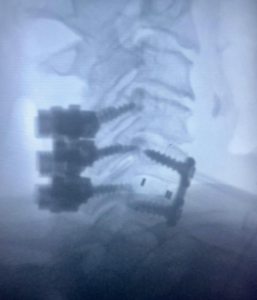

The first 2 pictures are a CT scan and then an MRI of the C5-6 fracture with spinal cord compression. The next is X-ray taken during surgery. The last is X-ray at 2 months postoperative. At 2 months after surgery, the patient is living at home again. She is as strong as ever!”